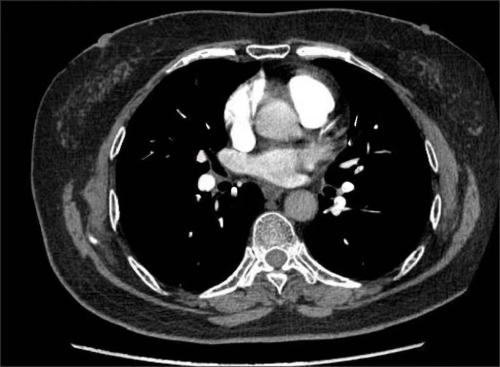

治疗后,肺动脉部分血管造影下栓塞明显减少

家住长沙的73岁刘女士,3个月前因“反复胸痛”先后于多家医院就诊,因曾怀疑为冠心病,虽服用了治疗冠心病药物,但症状未见好转,后来到湖南省人民医院心内四病区就诊。在仔细询问病史后,心内四病区陈美娟主任医师认为其胸痛可能是肺栓塞所致。经肺动脉CTA、双下肢静脉彩超检查,患者被确诊为肺栓塞。为防漏诊,患者进行了冠脉造影检查,结果显示冠脉光滑,没有冠心病。5月5日,刘女士在服用了抗凝药物治疗3个月后,复查肺动脉及双下肢静脉未见血栓,胸痛症状明显好转。